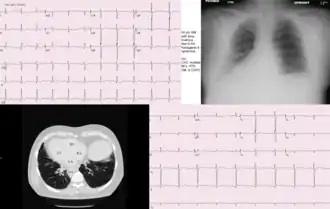

![]() Транспозиция органов при синдроме Картагенера | |

Синдром Картагенера характеризуется такими клиническими признаками, как транспозиция внутренних органов (situs viscerum inversus), аномалии мукоцилиарного клиренса, хронический бронхит, хронический риносинусит, хронический отит, мужское бесплодие.